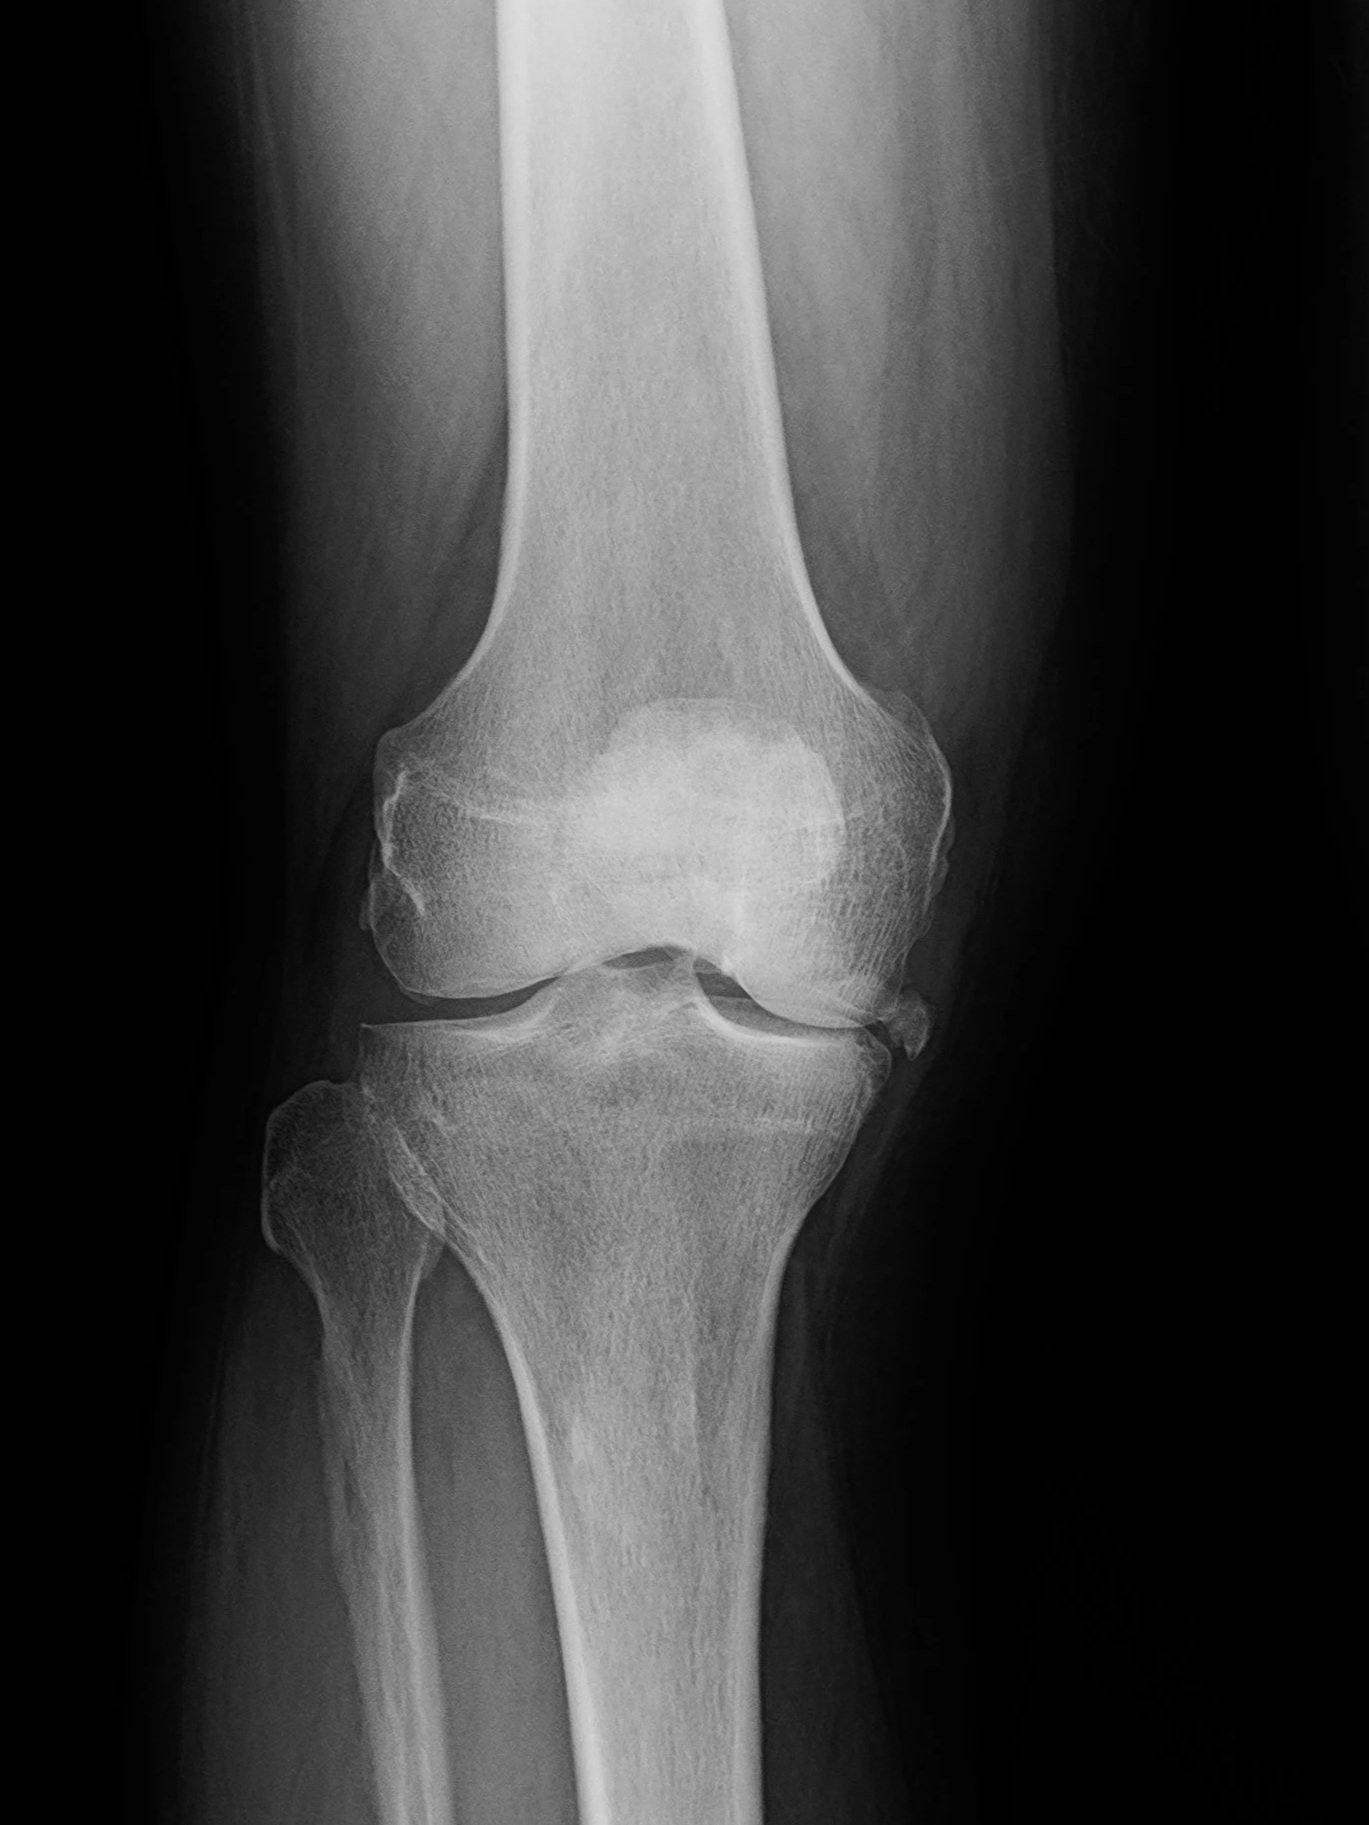

X-ray of knee showing joint space narrowing from osteoarthritis.

Before

Advanced osteoarthritis in the knee with loss of joint space and abnormal alignment. This causes pain, inflammation, and stiffness.